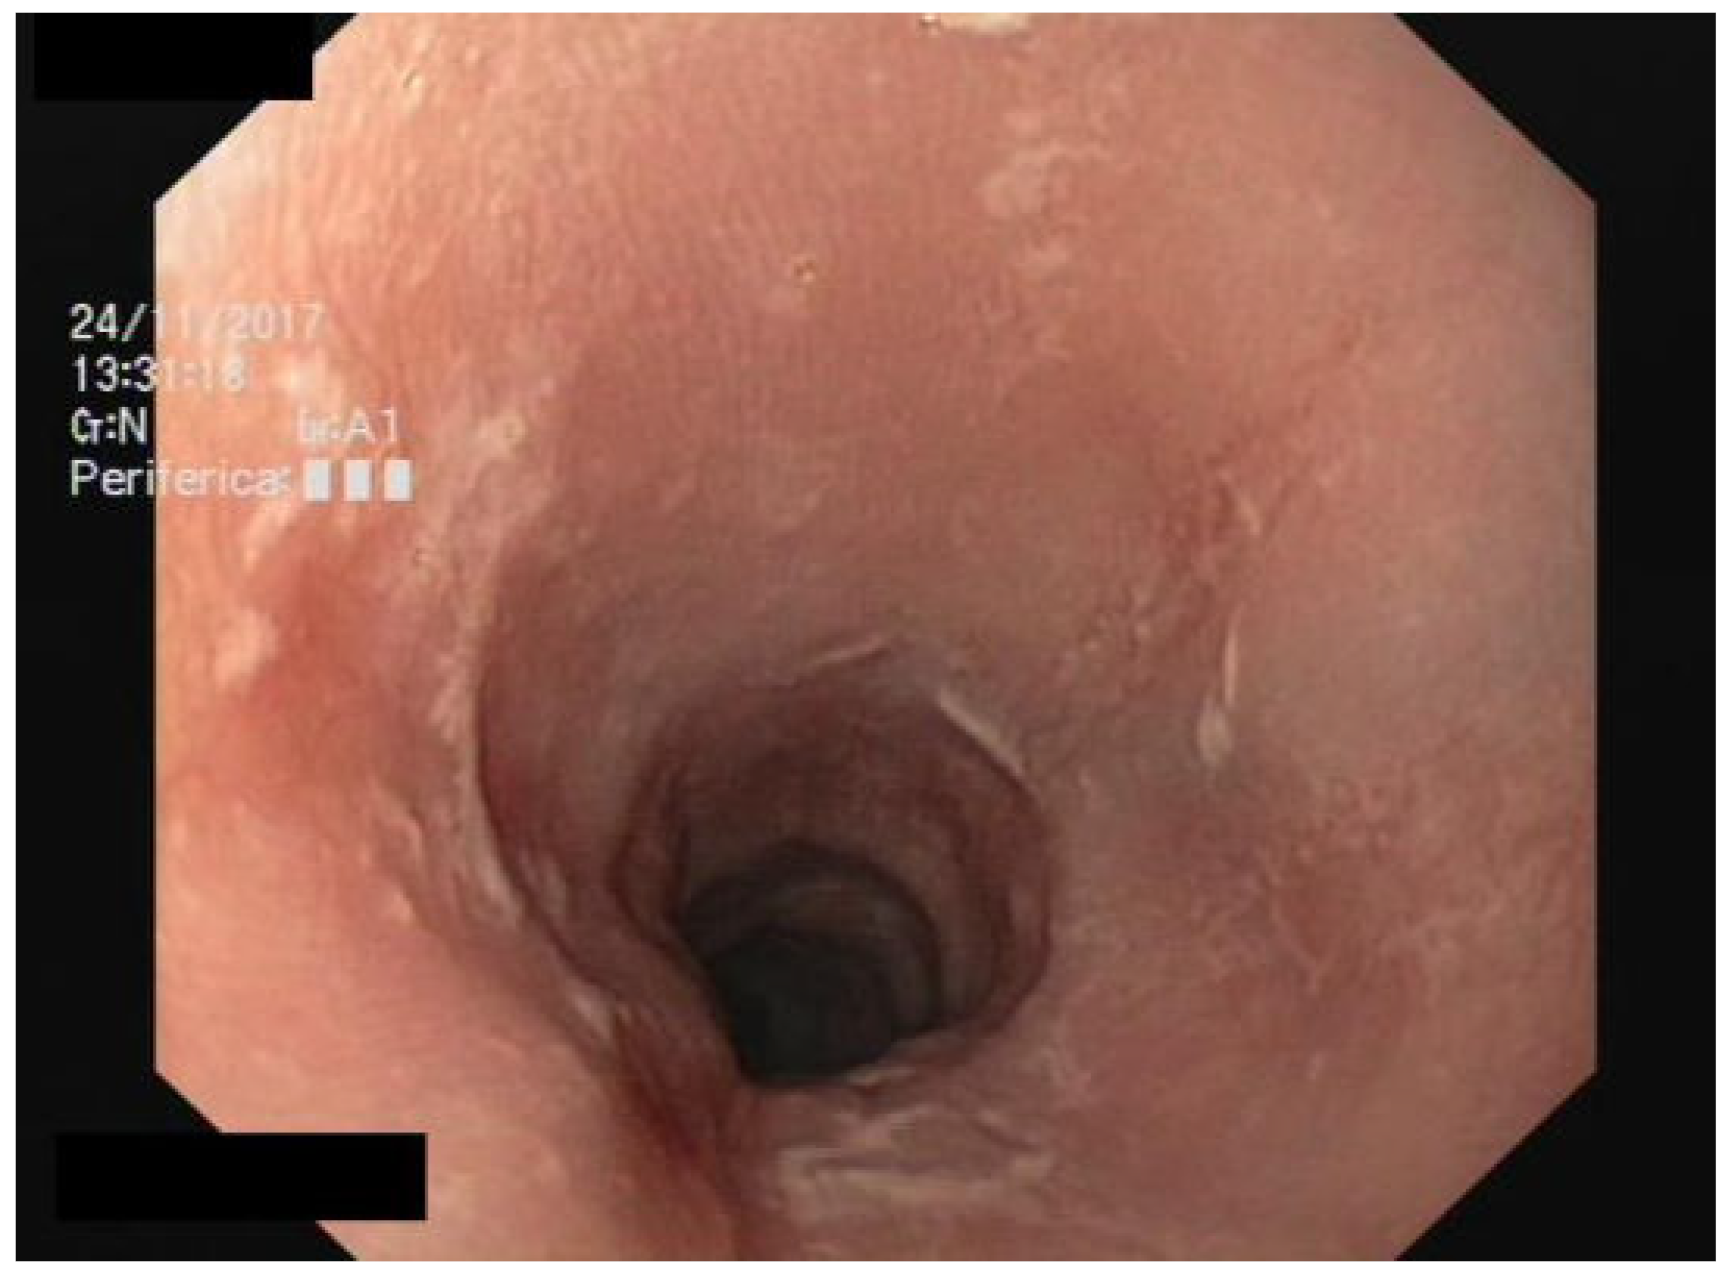

We performed a lateral–cervical spinal X-ray, a CT scan (Figure 2), and MRI (Figure 3) of the head, neck, and chest, which demonstrated anterior osteophytosis resulting in the compression of the esophagus between levels C2 and C5 and widespread axial spondylarthrosis. We also performed an esophago-gastric endoscopy, which showed a normal and undamaged esophagus, with whitish-pink cardiac mucosa and no motility disorders (Figure 4); in addition, the lumen appeared to present an ab extrinsic compression at its proximal tract. Given the absence of upper digestive endoscopy abnormalities, we initiated a logopedic and postural rehabilitative treatment.

Figure 4. Esophago-gastric endoscopy showing normal and undamaged mucosa of the esophagus.